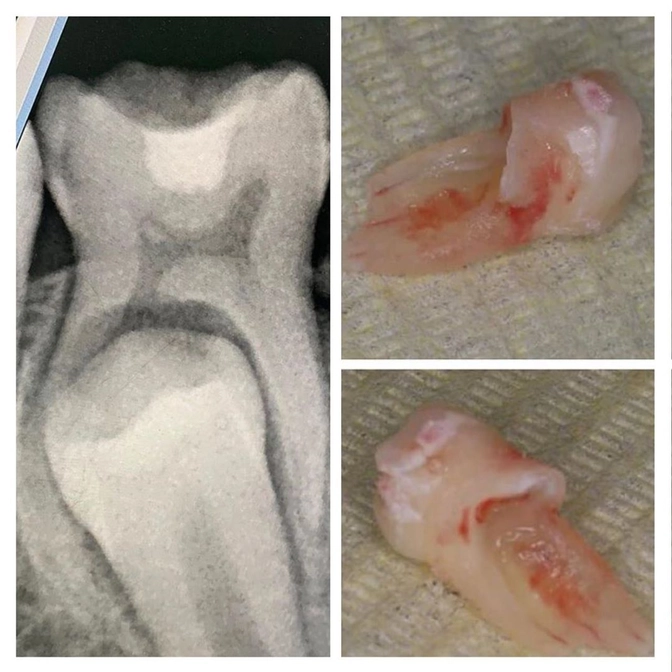

Пациентке 12 лет.

Этому зубу («Четверка») пора меняться (обычно это происходит в 9-10 лет).

С левой стороны молочный зуб уже сменился на постоянный, а с правой - никак не хочет покидать свое место и мешает прорезыванию "старшего собрата".

✔Для начала рентген.

Видим, что корни молочной "четверки" рассасываются неравномерно - один рассосался, а второй даже не думает.

Постоянный четвертый зуб прорезывается криво - это ортодонтическое показание к удалению молочного.

• Если вдруг кто забыл или не знал, напомню — у молочных зубов тоже есть корни.

Под (или над) молочными зубками развиваются зачатки постоянных.

К моменту смены зубов происходит «продвижение» зачатка постоянного зуба в сторону прорезывания.

Этот процесс провоцирует рассасывание корня молочного зуба.

Все ведь помнят, что молочные выпадают уже без корня?

Они рассасываются полностью, поэтому создается впечатление и бытует заблуждение, что у молочных зубов нет корней.

Они есть и весьма длинные!